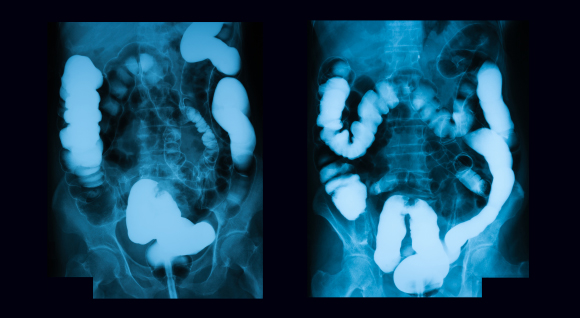

סרטן המעי הגס הוא הסרטן השני בשכיחותו בישראל, לאחר סרטן השד. צילום רנטגן של מטופל עם סרטן המעי הגס | Shutterstock, Suttha Burawonk